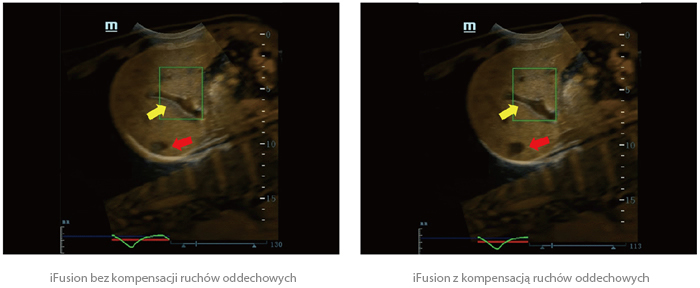

Fuzja obrazów z kompensacją ruchów oddechowych

Jest to pionierska, innowacyjna i ekskluzywna technologia kompensacji ruchów oddechowych Firmy Mindray, która wyznacza nowy poziom precyzji fuzji obrazów. Wspierana przez czuły magnetyczny sensor ruchu zapewniający dokładność co do milimetra, może pomóc w wyeliminowaniu zniekształceń i niedokładności połączenia obrazów spowodowanych oddychaniem pacjenta.

20180920133827_7027